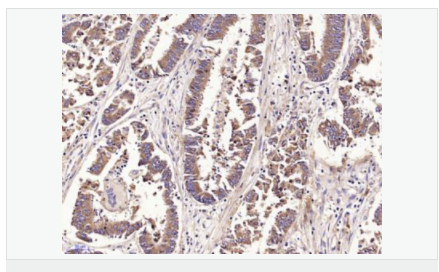

| 產(chǎn)品應(yīng)用 | ELISA=1:5000-10000 IHC-P=1:100-500 IHC-F=1:100-500 IF=1:100-500 (石蠟切片需做抗原修復(fù)) not yet tested in other applications. optimal dilutions/concentrations should be determined by the end user. |

| 產(chǎn)品介紹 | This gene encodes a protein which is a member of the calcitonin-related hormones. The encoded protein is involved in maintaining homeostasis in many tissues, acting via CRLR/RAMP receptor (calcitonin receptor-like receptor/receptor activity-modifying protein) complexes. Multiple alternatively spliced variants, encoding the same protein, have been identified. [provided by RefSeq, Dec 2011]. TISSUE SPECIFICITY:High expression detected in the submaxillary gland, kidney, stomach, and mesentery, followed by the pituitary, lung, pancreas, intestines, spleen, thymus and ovary. Expressed mainly in the intermediate lobe of the pituitary, with sporadic in the anterior lobe. Function: IMDL and IMDS may play a role as physiological regulators of gastrointestinal, cardiovascular bioactivities mediated by the CALCRL/RAMPs receptor complexes. Activates the cAMP-dependent pathway. Subcellular Location: Secreted. Tissue Specificity: Expressed in the esophagus, stomach, jejunum, ileum, ileocecum, ascending colon, transverse colon, descending colon and rectum. Expressed in myocardial cells of the heart, renal tubular cells, hypothalamus, and pituitary. Similarity: Belongs to the adrenomedullin family. SWISS: Q7Z4H4 Gene ID: 79924 Database links: Entrez Gene: 79924 Human Entrez Gene: 223780 Mouse Omim: 608682 Human SwissProt: Q7Z4H4 Human SwissProt: Q7TNK8 Mouse Unigene: 449099 Human Important Note: This product as supplied is intended for research use only, not for use in human, therapeutic or diagnostic applications. |